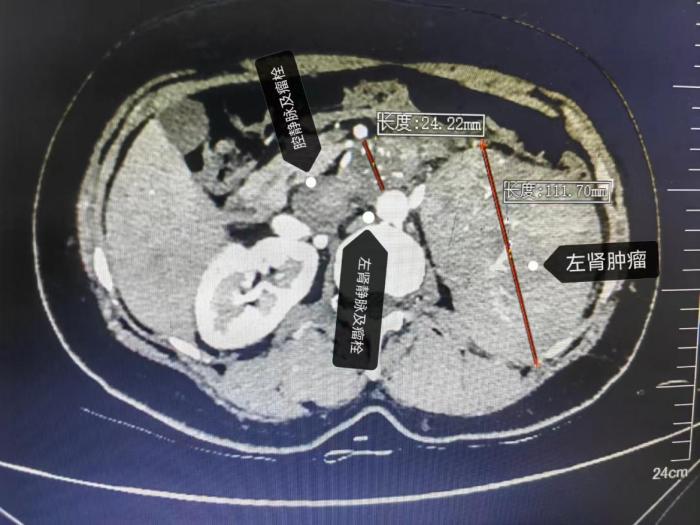

近日,45岁的黄女士日前因“间歇性尿血伴腰痛3天”就诊于南溪山医院。经检查结果发现一个直径超10cm的巨大左侧肾肿瘤且伴肾静脉瘤栓及下腔静脉瘤栓!目前肾癌伴肾静脉癌栓及下腔静脉癌栓最有效的治疗方法是行肾根治性切除术+肾静脉瘤栓取栓术+下腔静脉瘤栓取栓术,但手术中极易出现瘤栓脱落而导致猝死,手术风险极高,术中需精准分离下腔静脉、肾静脉等大血管,且该患者癌栓直径近3厘米,肿瘤巨大,导致空间狭小、分离困难。该手术是泌尿外科超高难度的标志性手术,也被称之为“皇冠上的明珠”。

泌尿外科主任廖松柏博士团队为其进行充分的术前检查及围手术期评估。为保证患者安全,为了给患者提供最佳的治疗方案,泌尿外科联合心脏大血管外科、手术麻醉科、重症医学科等多个学科的专家进行多学科联合会诊,结合患者病史、症状体征、影像学资料及国内外的治疗经验,对患者进行了全面评估,将术中可能遇到的情况及处理预案进行逐一推演,共同制定了围手术期的治疗与护理方案。考虑到患者做左肾肿瘤大,左侧肾静脉癌栓长,已充满整个肾静脉,并进入下腔静脉,而且癌栓直径粗,术中会粘连,手术难度大,出血多,为了减少术中出血量等问题,经泌尿外科团队联合多学科多次讨论,廖松柏主任亲切的与患者交流,缓解患者紧张的情绪,最终决定拟行在全麻下行左侧肾根治性切除术+左肾静脉瘤栓取栓术+下腔静脉瘤栓取栓术+下腔静脉缝合术。